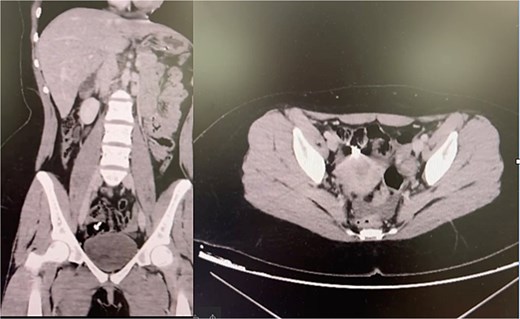

A 16-year-old boy with documented behavioral difficulties ingested a plastic sandwich bag. He presented 2 days later with colicky abdominal pain, vomiting, and distension. Radiographs showed dilated loops with a distal transition point. CT revealed obstruction in the distal ileum, but no clear intraluminal object was identified.

Conservative management with bowel rest and nasogastric decompression failed. Laparotomy revealed a folded plastic bag impacted in the distal ileum, which was removed via enterotomy (Fig. 2). Recovery was uncomplicated.

Teaching point: Adhesive obstruction is often presumed in adolescents with prior surgery, but FBI should be considered, particularly when symptoms persist or imaging is inconclusive [4, 10].